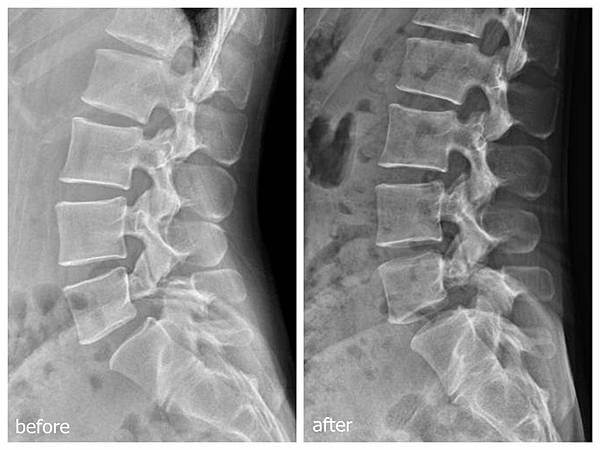

但是,我們泛指的結構改變,是活體上細微的變化,短時間內並不會直接反應在影像檢查上,就已經可以改善症狀,可是,如果從影像檢查中都可以看見改善,這是否可以證明,人體是可以還原的呢!?

這應該是椎弓裂(vertebral cleft),比較一下調整前後的差異,還有、照片裏還透露了什麼樣的訊息?這樣是變好還是變差?很有趣的!順便猜猜看,這樣的歷程、需要多久的時間?